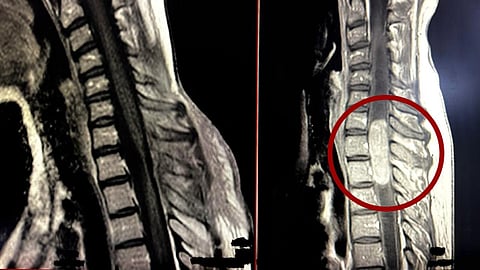

نجح فريق جراحة المخ والأعصاب في مدينة الملك سلمان بن عبدالعزيز الطبية بالمدينة المنورة في إجراء عملية نوعية معقّدة لاستئصال ورم داخل الحبل الشوكي يمتد من الفقرة العنقية السابعة (C7) حتى الصدرية الثانية (T2)، ومصحوب بتوسع نخاعي ضخم، في حالة تُعد من أعقد الجراحات العصبية على الإطلاق ولا يجريها إلا فرق طبية ذات خبرة متقدمة وتجهيزات عالية المستوى.

وأوضح تجمع المدينة المنورة الصحي أن المستفيدة، البالغة من العمر 38 عامًا، حضرت وهي تعاني من أعراض عصبية متفاقمة استمرت عدة أشهر، شملت اضطرابات حسية وصعوبة في الحركة. وأظهرت الفحوصات الإشعاعية وجود ورم تسبب في توسعات شديدة داخل القناة المركزية للنخاع الشوكي، ما جعل التدخل الجراحي بالغ الدقة والخطورة.